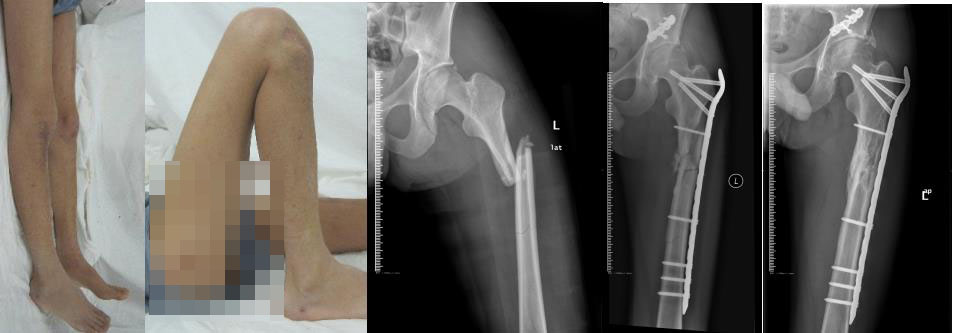

同一患者右胫骨平台骨折及左股骨长段骨折。微创复位内固定治疗,术后3周关节活动功能已恢复正常。